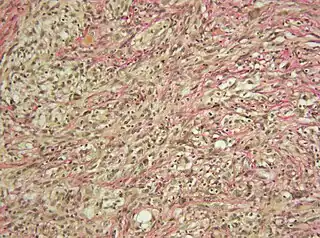

![]() Microfotografía de un gliosarcoma. | ||

El gliosarcoma es un tipo de neoplasia cerebral. Se caracteriza por presentar un componente glial y otro sarcomatoso. Se considera una variante poco frecuente del glioblastoma, aproximadamente el 2,1% de todos los glioblastomas son gliosarcomas. Tiende a diseminarse infiltrando los tejidos próximos, entre el 11 y el 15% de los casos provoca metástasis por diseminación a otros órganos, principalmente a los pulmones, el hígado y los ganglios linfáticos. La epidemiología de los gliosarcomas es similar a la de los glioblastomas, la edad media de aparición es 54 años, es más habitual en hombres que en mujeres y se presenta con más frecuencia en el lóbulo temporal del cerebro.[3]